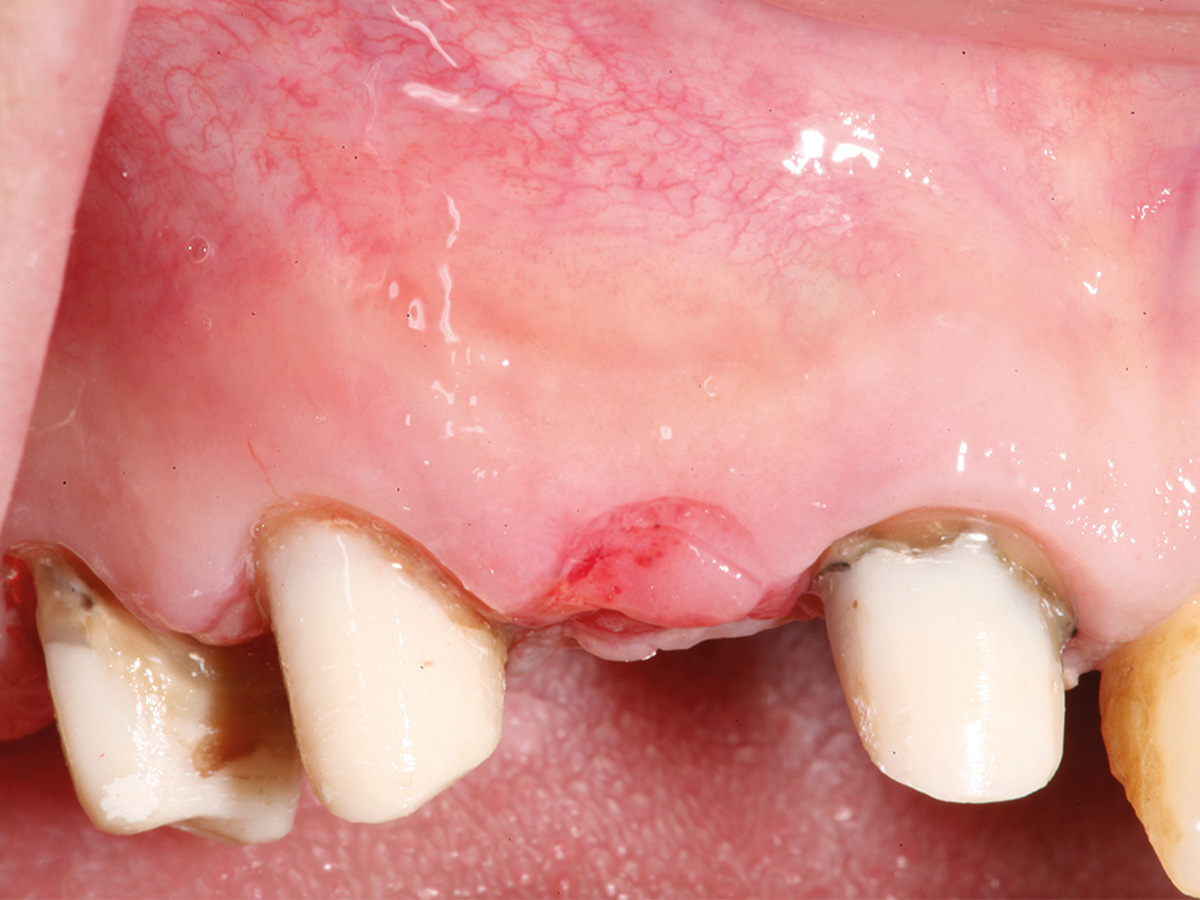

Abbildung 9

6 Monate post-OP nach Freilegung. Zu beachten ist der Alveolarkamm im Gegensatz zum Ausgangsbefund.